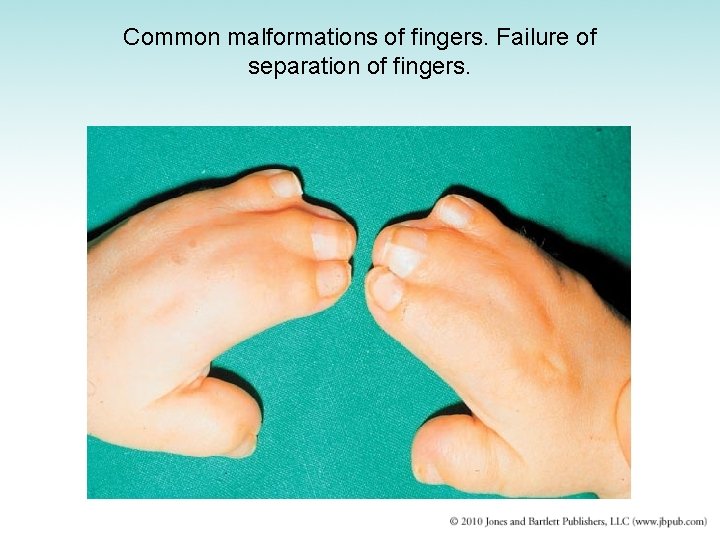

Congenital Malformations (1 of 2) • Achondroplasia – Faulty endochondral bone formation – Impaired growth of extremities and formation of skull bones – Causes dwarfism with disproportionately short limbs • Osteogenesis imperfecta – – – Thin and delicate bones easily broken May be born with multiple fractures Malformation of fingers and toes Extra digits or polydactyly Easily removed Fused digits more difficult to correct

Common malformations of fingers. Failure of separation of fingers.